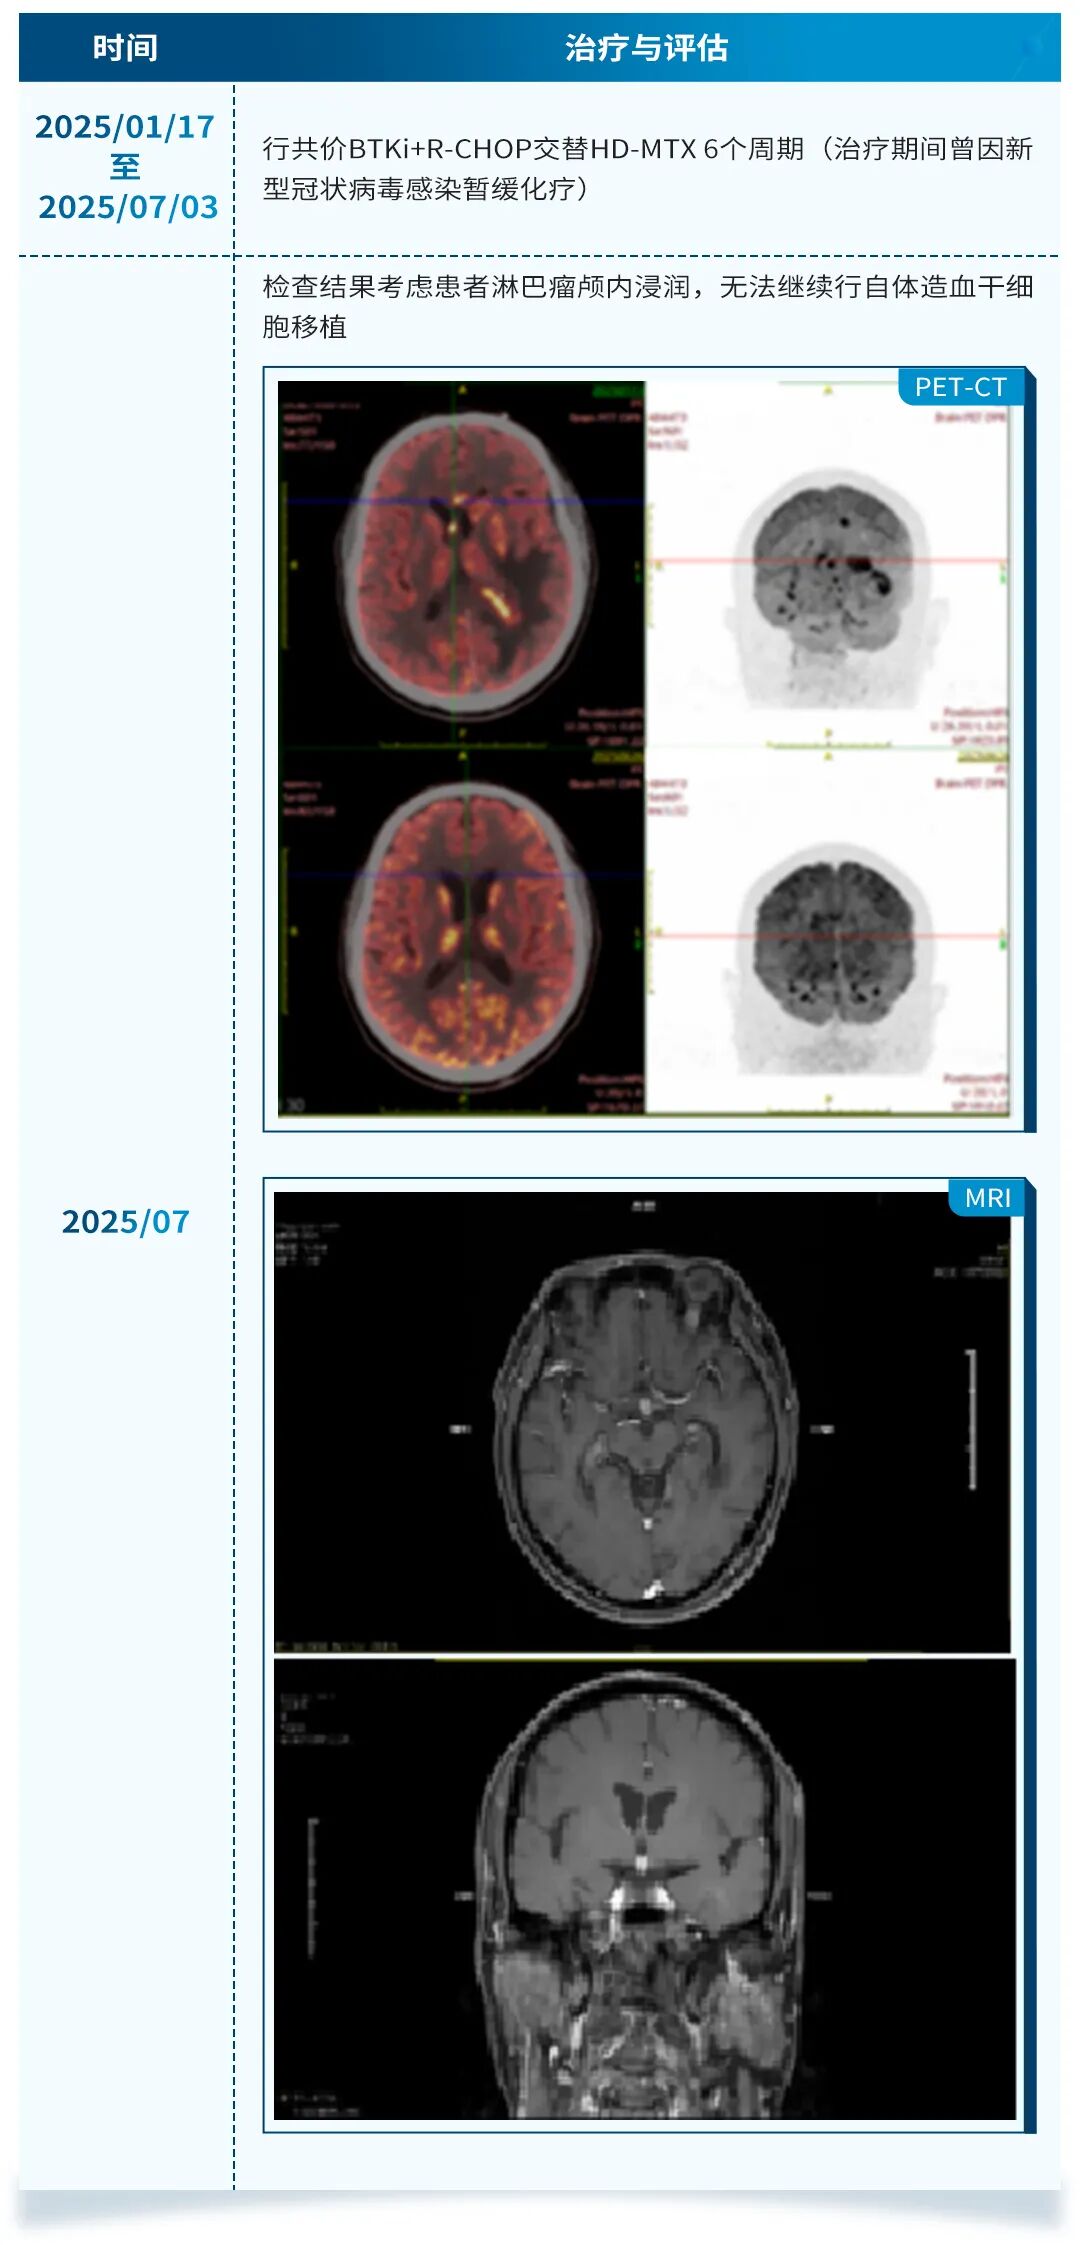

本次分享2例患者均为IVLBCL患者,其中1例为共价BTKi联合方案治疗后出现淋巴瘤颅内浸润无法继续行自体造血干细胞移植(ASCT)改用匹妥布替尼联合塞替派的治疗,2个周期治疗后获得了CR并成功进行ASCT;另一例为初诊患者,一线治疗直接选择匹妥布替尼联合Pola+R-CHP,3个周期治疗后获得了CMR,后续会考虑序贯ASCT。这两个病例提示匹妥布替尼联合治疗方案在IVLBCL患者中具有良好的疗效与安全性。未来还需更更大规模的人群以及随机对照研究来证实匹妥布替尼联合方案在IVLBCL患者中的疗效与安全性,以改善此类患者的生存结局。此外,IVLBCL患者复发后的生存极差,如何避免或延缓复发是临床关注的另一问题。缓解后序贯ASCT巩固治疗的IVLBCL患者的3年PFS率和OS率分别为83%和89%,3年累积复发率为14%[7][8]。因此,本次分享的两个病例均考虑在治疗缓解后进行ASCT。